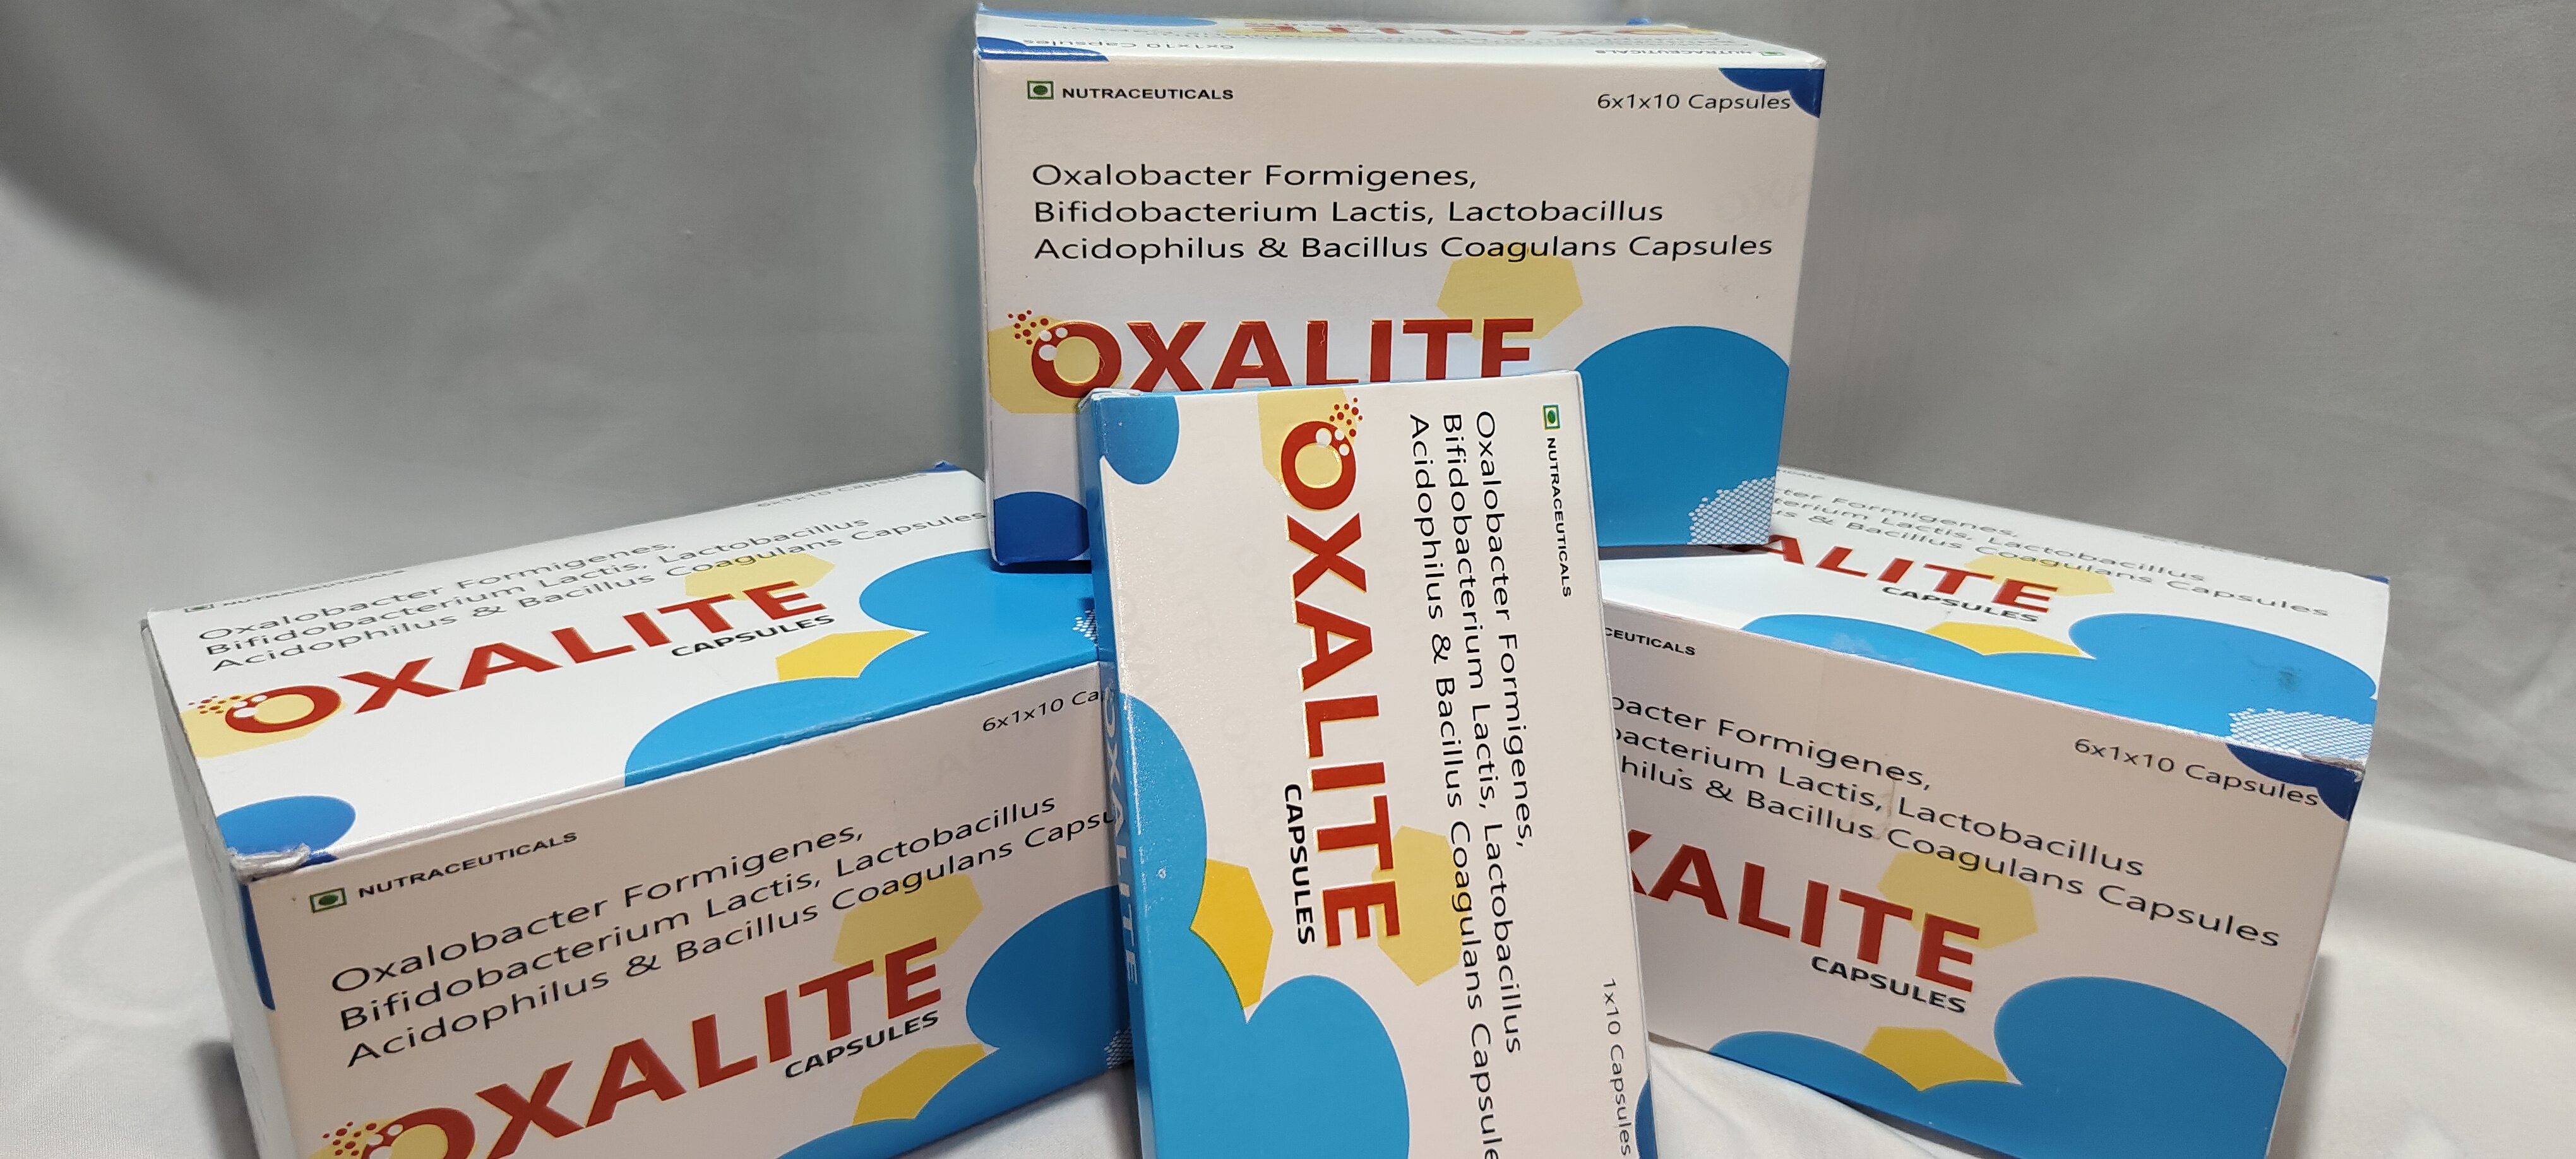

What are OxaLite Capsules?

OxaLite Capsules contain a potent blend of probiotics, including Oxalobacter formigenes, Bifidobacterium lactis, Lactobacillus acidophilus, and Bacillus coagulans. These probiotics work synergistically to reduce kidney stones formed due to excess oxalates.

Is the product certified by relevant health authorities or organizations?

You can View it Below